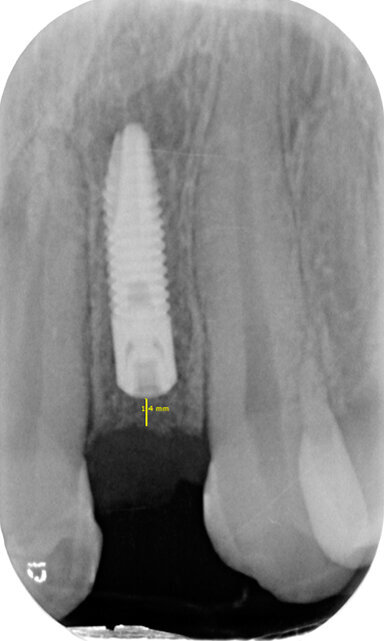

Fig. 4a - Rx endorale pre-operatoria sito edentulo sede 22. Misurazione dello spazio inter-radicolare per l’inserimento dell’impianto.

Prima dell’inizio dei lavori implanto-protesici e al termine del trattamento ortodontico della durata di circa un anno, è stato eseguito un condizionamento di tessuti molli nel sito edentulo tramite rifacimento della protesi tipo Maryland in sede 22. Utilizzando le sezioni CBCT e le ricostruzioni 3D è stata poi eseguita la progettazione virtuale del caso, simulando il posizionamento dell’impianto nel sito preparato ortodonticamente il cui alloggiamento ottimale è stato individuato come al centro del futuro elemento protesico13. Dopo l’esecuzione di un lembo di accesso a tutto spessore, si è proceduto alla preparazione del sito implantare. È stata eseguita una procedura di rigenerazione ossea in sede 22 con Bio-Oss 0.5 e Bio-Gide 25 x 25; è stato poi posizionato un impianto di 13 mm e diametro 3 mm, con particolare attenzione alla tridimensionalità mesio-distale, vestibolo-palatale e apico-coronale (Figg. 4a, 4b). A sette mesi dalla prima fase chirurgica è stata effettuata la seconda fase chirurgica per il posizionamento della vite di guarigione.